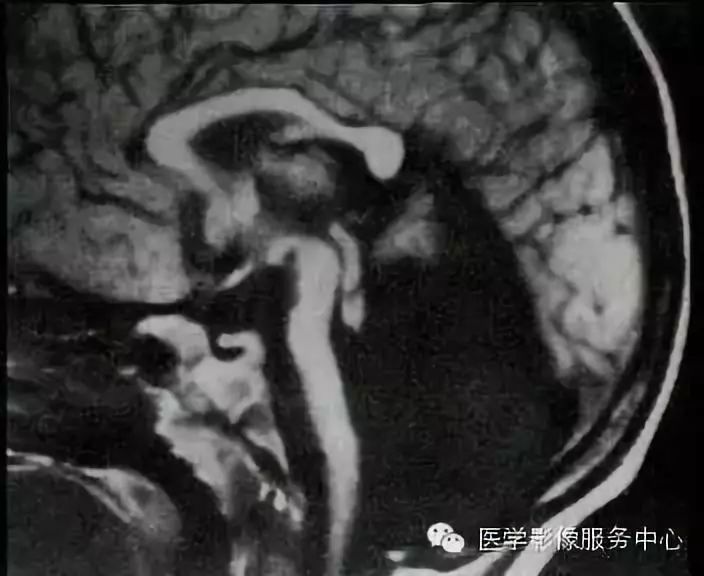

Chiari畸形II型 (图源见水印)

Chiari畸形II型(CM-II):通常与脊髓脊膜膨出(一种神经管闭合不全的先天性畸形)相关,常见于婴儿。几乎所有患者均合并脊髓空洞和脑积水。